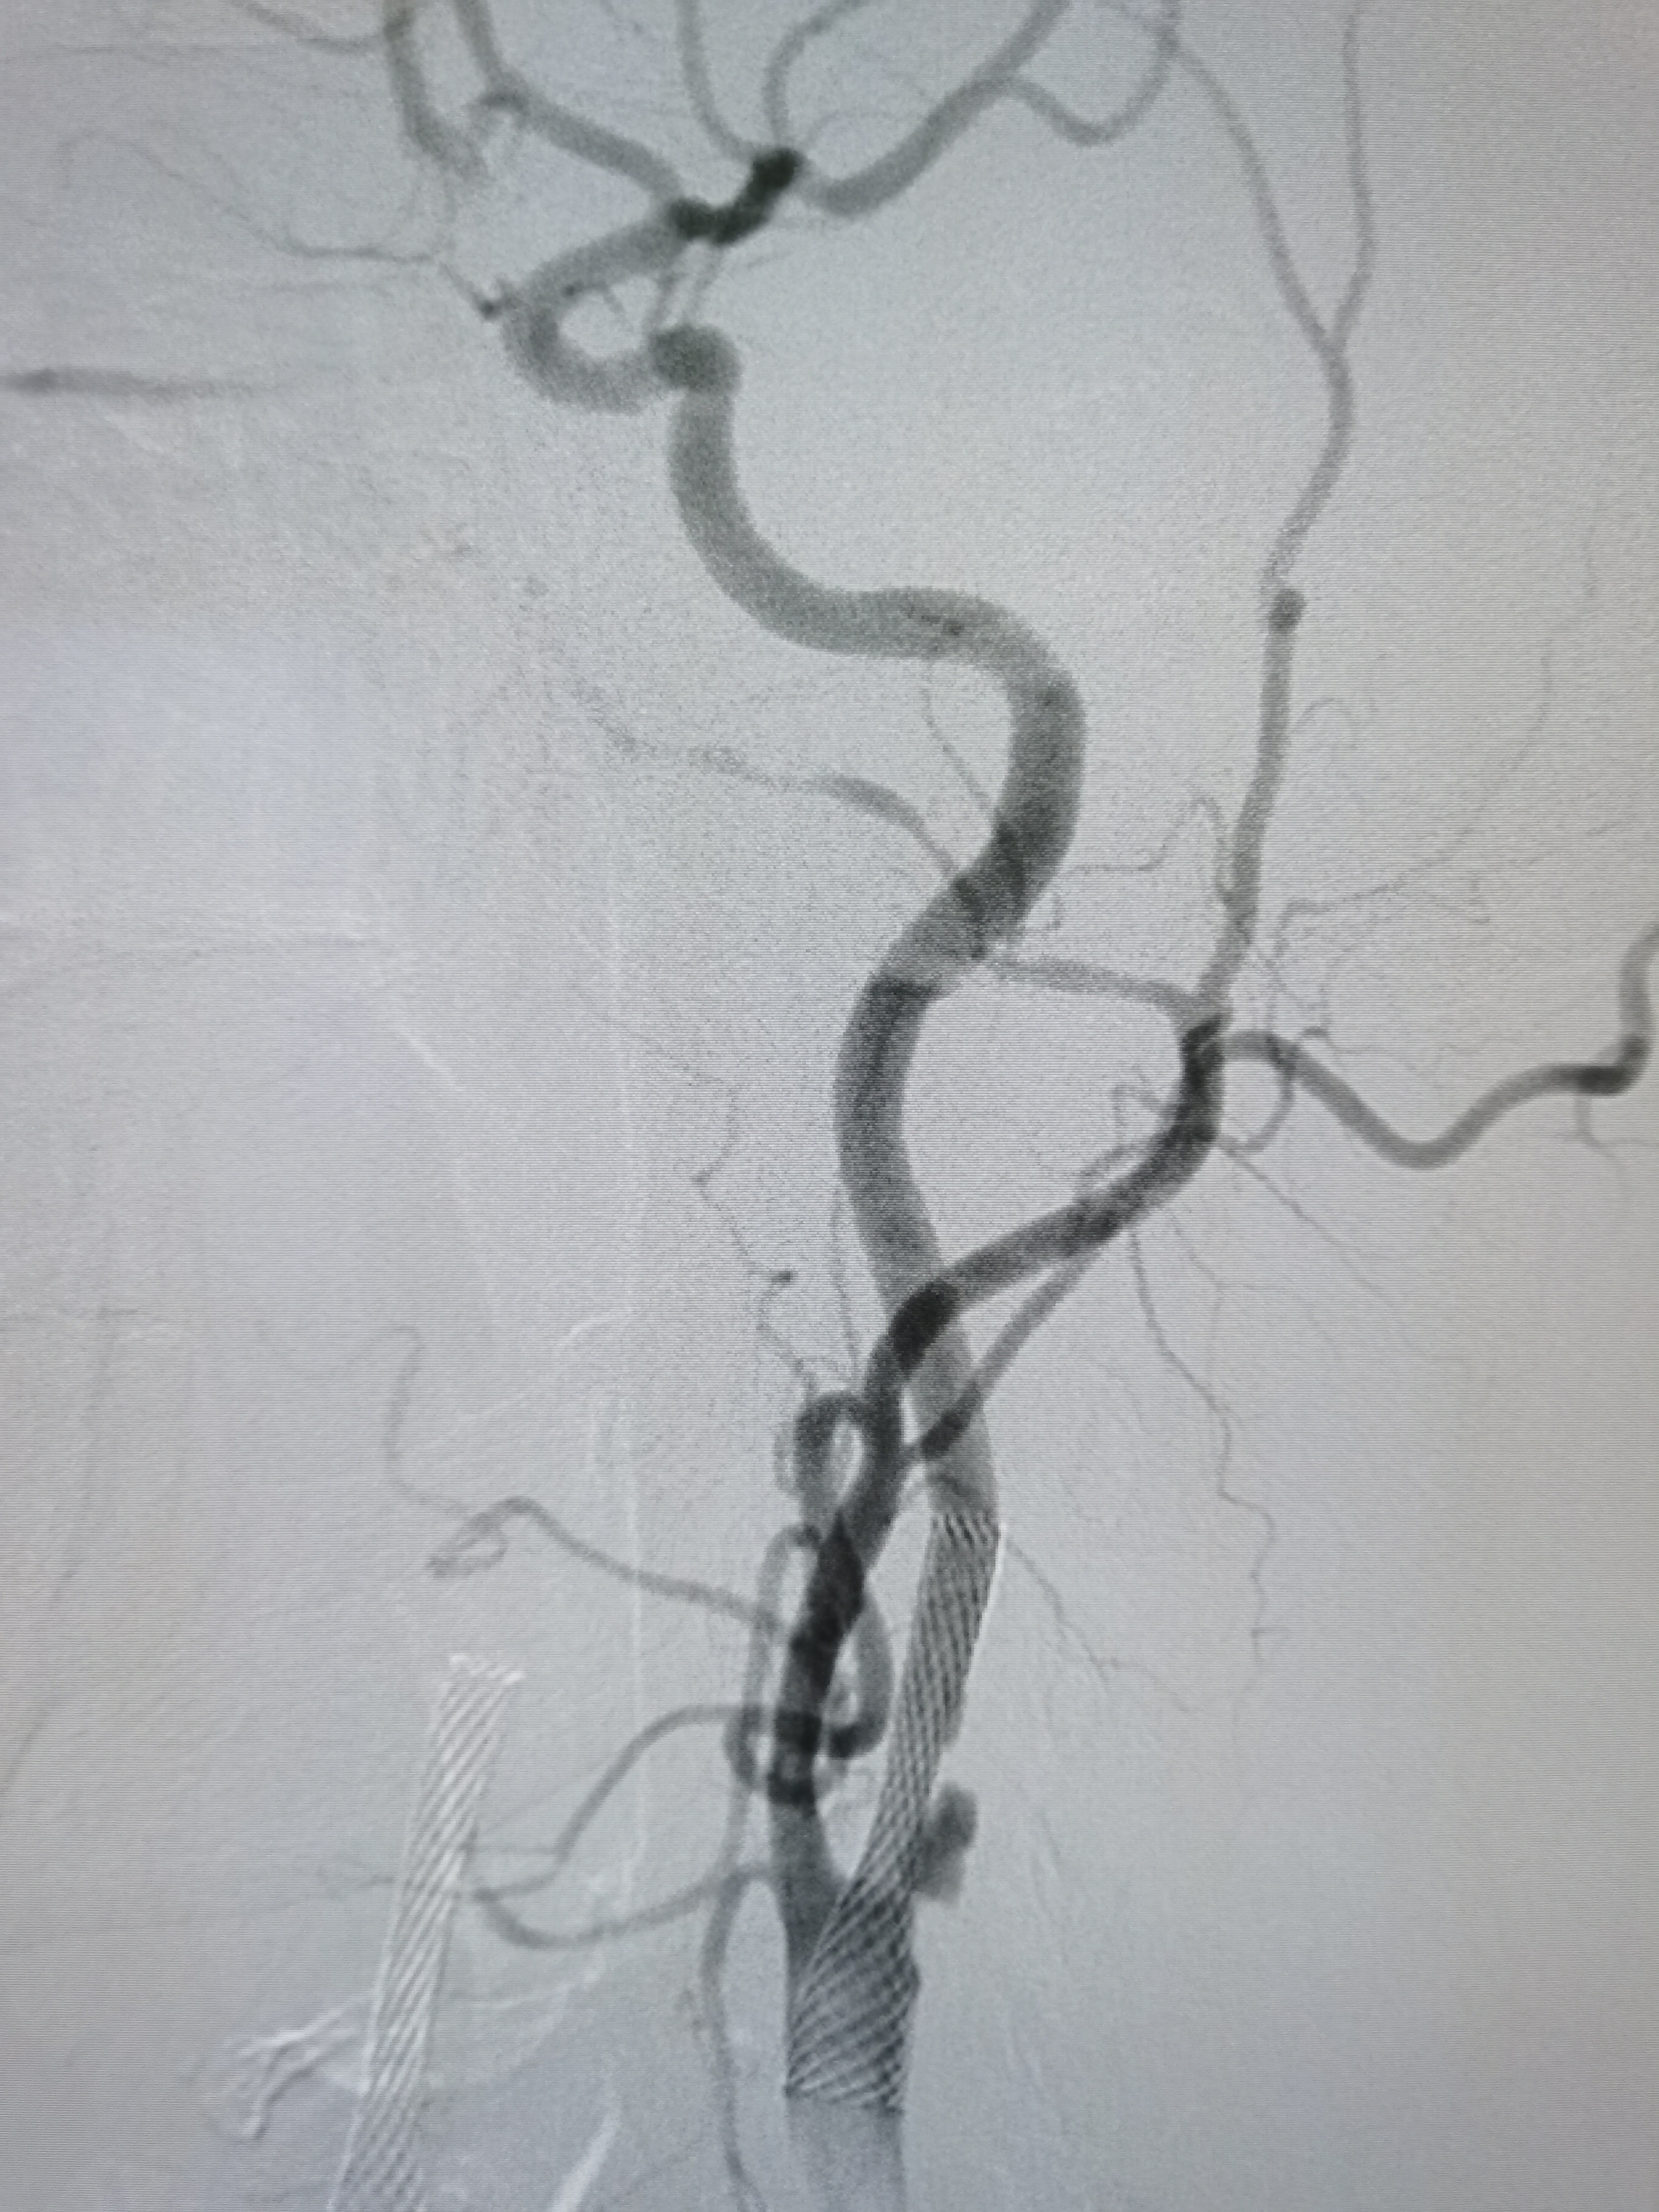

8F导引导管到位右侧颈总动脉末端,明确狭窄。

微导丝顺利通过病变,交换入远端保护伞。

2/20,4/30球囊渐进性预扩后狭窄改善。

9/30支架定位后释放。

支架释放后狭窄解除。

支架释放后颅内血供改善。

颅内血供良好。